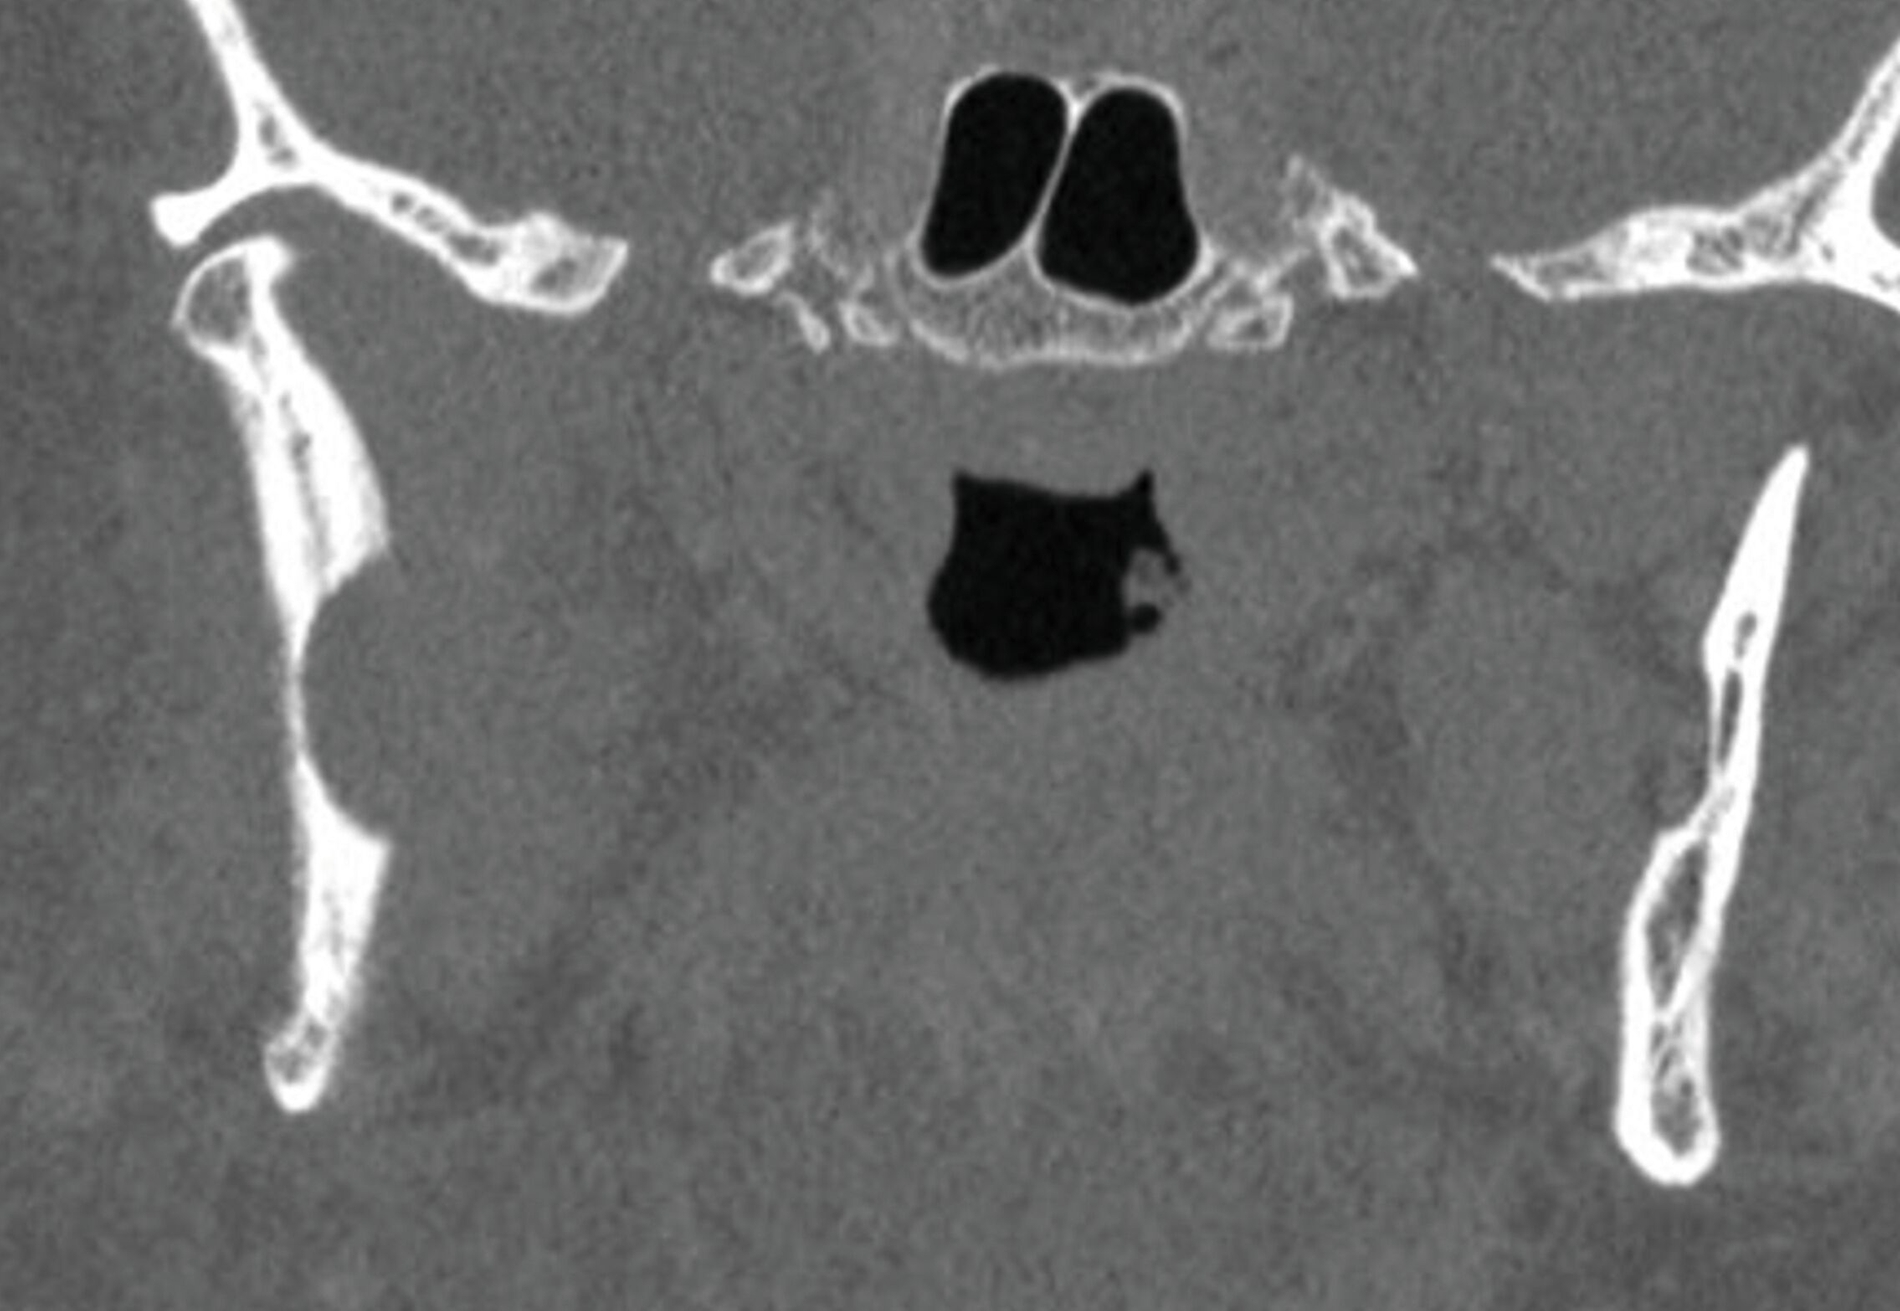

Ein 75-jähriger Patient stellte sich zur Nachkontrolle nach der Entfernung einer Keratozyste im rechten Unterkiefer vor, die vor mehr als fünf Jahren in einer anderen Einrichtung durchgeführt worden war. In der Zwischenzeit war aufgrund eines perimandibulären Abszessgeschehens in derselben Region eine extraorale Inzision vorgenommen worden. Die Panoramaschichtaufnahme zeigte im Vergleich zur Voruntersuchung eine fortschreitende multifokale Osteolyse des rechten aufsteigenden Unterkieferasts, was sich durch die ergänzende Computertomografie bewahrheitete (Abbildung 1). Eine enoral durchgeführte Probeentnahme bestätigte die Arbeitsdiagnose eines Rezidivs der zuvor diagnostizierten Keratozyste.